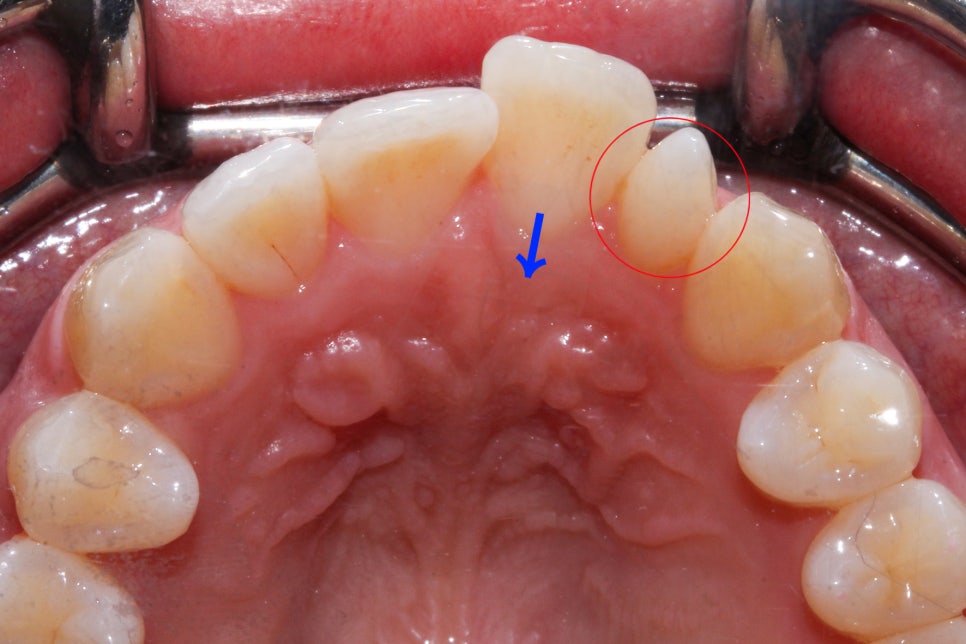

뻐드렁니 교정 전 상악과 하악의 교합면 사진입니다.

상악 교합면을 확인해보면 중절치가 순측으로

뻐드러져 나간 모습을 볼 수 있는데요,

기준치의 역할을 하는 송곳니의 위치가

좋기 때문에 발치 없이 비발치 교정으로

치아를 교정할 수 있을 것으로 예상됩니다.

하악의 경우 상악보다 전치부의 crowding이

심한 모습을 확인할 수 있는데요,

왼쪽 구치부의 교합상태가 하악이

상악보다 후방에 위치하고 있기 때문에

(2급 부정교합) 이를 해결하기 위한

교정 계획 수립이 필요할 것으로 보입니다.